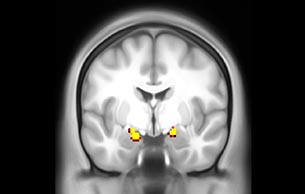

BOLD fMRI activation, depicted in color, of left anterior insula (MNI plane z = 8 mm) in a single subject by a contrast between viewing and matching faces with negative emotion (angry, sad, scared) versus happy faces. The voxelwise threshold is p < 0.001, and colored voxels survive false discovery rate correction to p < 0.05. The activated voxels in color are overlaid on the subject's own 3D-TFE image displayed in grayscale, after transforming the data to MNI space. The fMRI pulse sequence was a single shot FFE echo planar acquisition using MultiBand SENSE factor 6, dS SENSE factor 1, isotropic voxel size 2.4 mm, 60 transverse slices, TR 950 ms, TE 30 ms, flip angle 52 degrees, 517 dynamic scans, total scan duration 8:21 minutes. Image provided by James M. Bjork, PhD, Associate Professor of Psychiatry at VCU.

Emotional n-back task combines a test of working memory with the use of emotive (faces) and neutral (places) images. The contrast in the images is between the activity when faces are presented compared to places, showing activation in the amygdala, fusiform, and occipital face areas.

Processing based on the Human Connectome Project (HCP) pipelines. The high resolution of the fMRI data allows extraction of the cortical surface, with minimal averaging of non-cortical signal. Surface based analysis provides improved cross-subject alignment, and prevents signal contamination between adjacent sulci.

Group analysis of 88 9- and 10-year olds part of ABCD, all scanned at UVM on Philips Achieva 3.0T dStream. Scale runs from red p=0.001 to yellow p<10ˆ-5. Images provided by Dr. Watts.

Acquisition using the ABCD protocol for fMRI with TR 800 ms, TE 30 ms, flip angle 52°, 2.4 mm isotropic imaging resolution with a 216×216×144 mm3 field of view using a MultiBand acceleration factor of 6 (60 slices, no gap). Two runs of 5 minutes per subject.